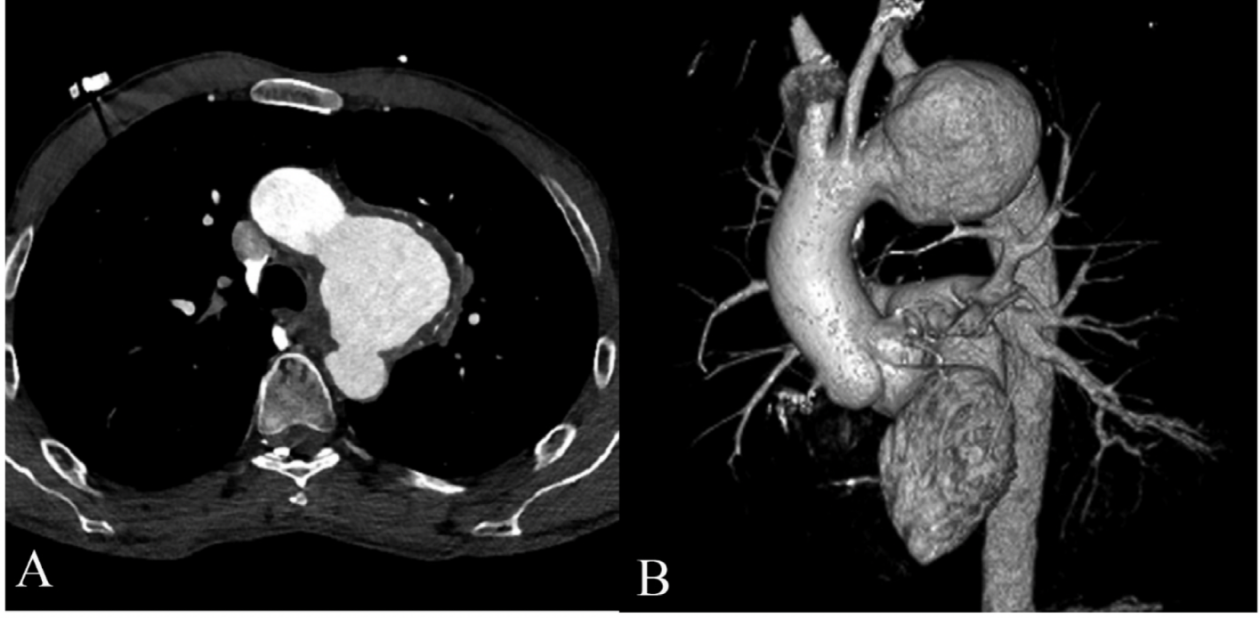

患者双臂血压125/85 mmHg,心率正常85 bpm。体格检查的其余部分都很正常。螺旋CT血管造影显示主动脉弓有一个巨大的动脉瘤,从左颈总动脉的起点开始,并延伸到降主动脉第一节(图1A-B)。仔细寻找动脉瘤部分与气道之间的联系,但没有发现任何联系。由于过去几天有大量咯血病史,因此开始为患者提供紧急治疗;因此,应用了混合程序。

图1: A)主动脉瘤螺旋CT血管造影。B)动脉瘤三维重建后